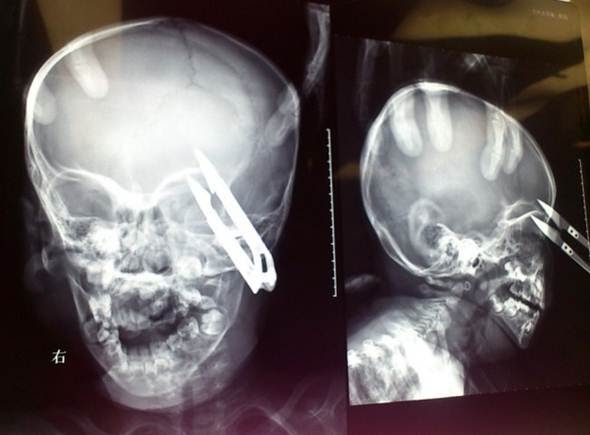

Um menino de dois anos de idade, sobreviveu milagrosamente depois de cair sobre uma tesoura que perfurou sua órbita ocular.

Wang Jierong, do oeste da China, estava correndo ao redor de sua casa com a tesoura na mão, quando tropeçou e caiu, afundando a tesoura acima do olho esquerdo.

O menino foi levado para o Hospital da Universidade de Lanzhou em Wushan County, onde os médicos realizaram uma cirurgia de emergência para remover o objeto.